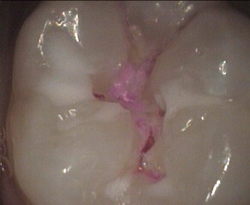

failed sealant has decay restored with white filling

old leaky sealant and decay restored